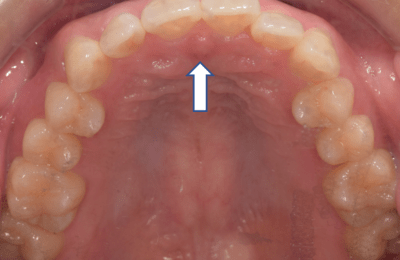

舌が下に落ちている場合

(お口ポカン、歯ぎしり食いしばりが多い、舌で歯を押してしまう方)

→舌の正しい位置を把握するトレーニング

安静時、舌の先は正しい位置にありますか?

舌をいつもつけておく位置を覚えましょう

- 上の前歯の1cm内側の歯ぐきのくぼみに舌の尖端をおく。

- 舌全体を上あごにつける

→舌全体を口蓋に挙げるトレーニング

①舌全体を口蓋に吸いつけ、ゆっくりと開ける

②ポンと舌打ちをする

③30回繰り返す

※舌の先はスポットにつけ、丸めないように注意しましょう!